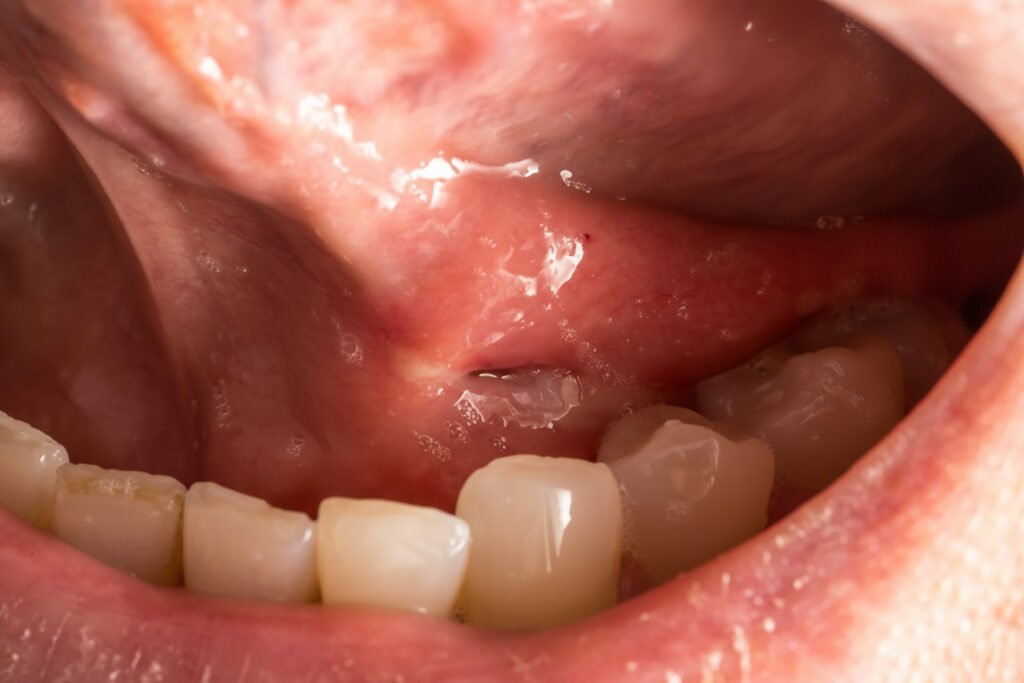

The symptoms of pericoronitis typically develop around wisdom teeth, especially when the tooth is partially erupted and covered by a flap of gum tissue called the operculum. The presence of this gum flap creates a pocket where food particles and bacteria can get trapped, setting the stage for infection and swelling. The gum tissue around the wisdom tooth can become red, tender, and inflamed, making it uncomfortable to chew or even to open your mouth fully.

Pericoronitis symptoms can range from mild discomfort to severe, debilitating pain that interferes with daily activities. Local symptoms typically begin around the affected wisdom tooth and may include intense, throbbing pain that worsens when biting down or chewing. The gums around the tooth become swollen, red and tender to the touch, often accompanied by a bad taste in the mouth and bad breath.

Many patients report difficulty chewing on the affected side, and the inflammation makes it hard to fully open the mouth. Pus may drain from the area around the tooth, creating an unpleasant taste and odour that persists despite brushing and mouthwash.